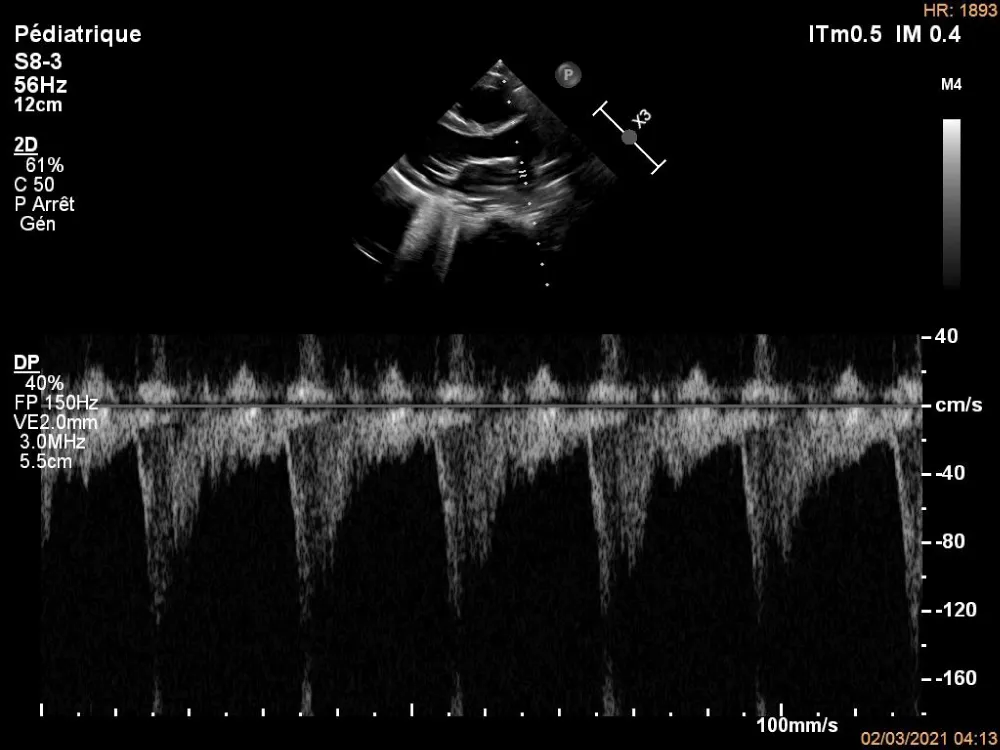

Figure 2: Pulsed Doppler echocardiography on the right pulmonary artery.

The electrocardiogram showed bi-atrial and left ventricular hypertrophy. On frontal telethorax, cardiomegaly with a supra-diaphragmatic peak, a right inferior arch overhang, and peri-hilar vascular overload, predominantly on the right. Cardiac ultrasound revealed a situs solitus heart with levocardia. The aorta normally emerges from the left ventricle, without obstruction. After a few centimeters, it gave way to a right pulmonary artery that filled correctly in systole without obstruction (Figures 1,2). The left pulmonary artery arises directly from the right ventricle. All cardiac cavities are dilated—suprasystemic pulmonary hypertension with ostium secundum-type atrial septal defect with right-to-left shunt. Cardiac angioscan confirmed the diagnosis, showing a 13 mm right pulmonary artery arising from the aorta. The left pulmonary artery arises directly from the right ventricle and measures 9.73 mm, with a functional pulmonary valve (Figures 3,4). Biological tests revealed microcytic hypochromic anemia at 9.3 g/dl. Medical treatment was based on furosemide, captopril, and spironolactone. A surgical cure after catheterization with reimplantation of the right pulmonary artery was indicated. The child died before surgery.